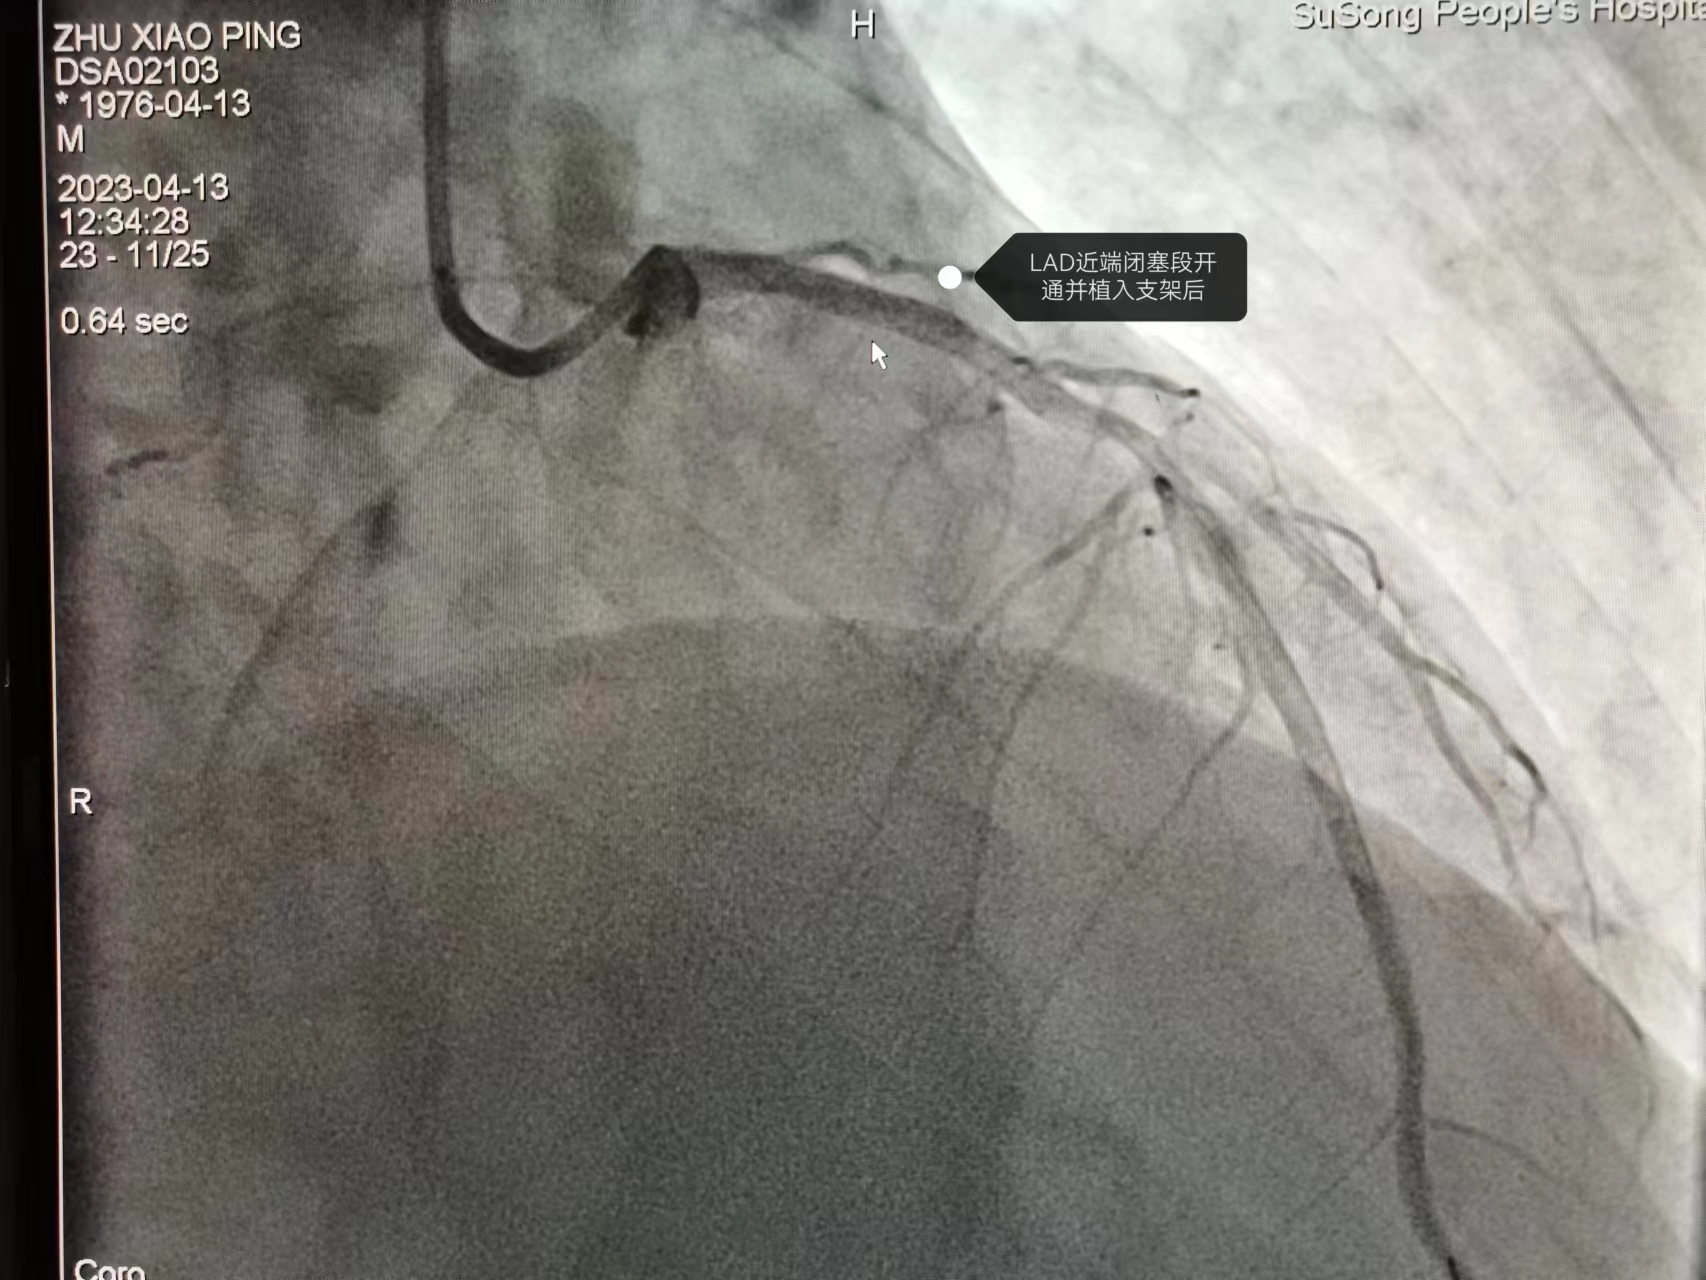

今年46岁、家住隘口乡的祝某,上午9:42在我院做心电图后没及时离开,随后说还有些不舒服,在心电图室再次做心电图提示急性广泛前壁心梗。然而,患者病情变化始料未及,10 时02分,患者突发意识不清,四肢抽搐,触摸大动脉搏动消失,患者呼吸心跳骤停。至此,一场与死神的赛跑拉开帷幕。临床电生理学中心主任李江琴和徐秀春、张敏医生轮流心肺复苏并立即启动院内发生ACS救治流程联系胸痛中心团队。在医务科主任贺叔书统一调度下,急诊科、ICU、麻醉科、导管室、心内科主任马成亮等胸痛中心专家团队十几名医护人员迅速展开救治,通力合作,上演了一场与死神赛跑的生死时速。大家紧张地忙碌着,给予电除颤7次、静脉推注抢救药、气管插管、呼吸机辅助呼吸等......经过一个多小时的抢救,患者自主心跳终于恢复、但仍然无自主呼吸。考虑随时有恶性心律失常及心跳骤停风险,在ICU行呼吸支持下转运至导管室。在导管室团队密切配合、麻醉科全麻呼吸支持下,马成亮主任带领张守刚、杨凯等医生行急诊PCI治疗。开通闭塞的前降支血管,植入一枚支架,术后患者心电图ST段下降>50%,TIMI血流恢复3级,患者心肌得到有效再灌注。

从上台至开通患者血管,仅用时29分钟,至此,此次抢救暂时告一段落,患者闭塞的血管再通,患者存活概率大大增加,术后转入ICU治疗。